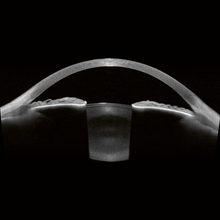

En tant que base de la plateforme ANTERION, l’App Imaging se concentre sur la visualisation haute résolution de l’ensemble du segment antérieur, de la surface antérieure de la cornée à la surface postérieure du cristallin. Elle fournit des images OCT à source balayée impressionnantes et révélatrices qui apportent une confirmation visuelle et ajoutent de la fiabilité et de la précision au diagnostic et au suivi des altérations du segment antérieur.

L’application Metrics de l’ANTERION présente des images OCT à source balayée d’une clarté exceptionnelle avec la chambre antérieure affichée en vue radiale.

Les images OCT haute résolution constituent la base idéale pour des mesures précises. Déterminez les paramètres d’angle prédéfinis ou effectuez des mesures à main levée adaptées à chaque cas clinique. Outre les paramètres couramment utilisés, l’application Metrics propose la mesure de la profondeur de la chambre antérieure, ainsi que de l’épaisseur et la courbure du cristallin.